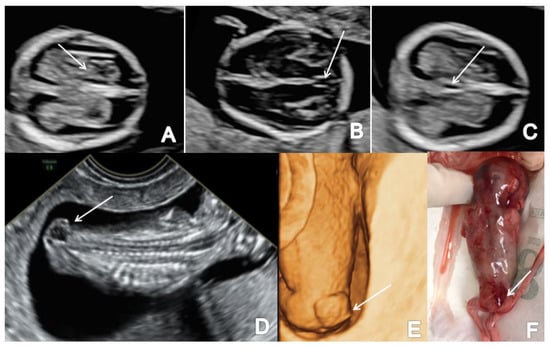

Figure 8.

First-trimester ultrasound images of a fetus with hydrocephaly (Case 11): (A) enlarged cerebral ventricles with shrinked choroid plexus (axial view); (B) increased third ventricle (axial view); (C) abnormal sagittal view with increased forth ventricle and cisterna magna (arrow); (D) sagittal view with an important disproportion between head and body and frontal bossing (arrow).